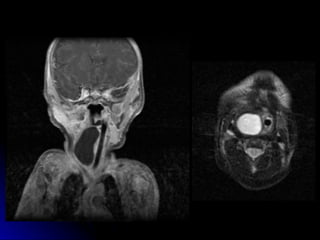

Foregut duplication cyst

Foregut duplication cyst

lymphangioma